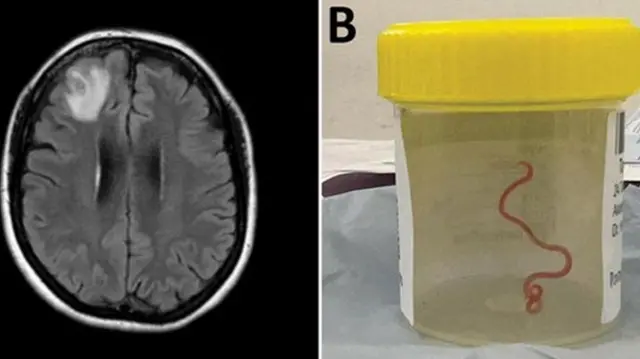

A karo na farko, masana kimiyya sun gano tana mai tsayin inci uku da ranta a ƙwaƙwalwar wata mata 'yar Australia mai shekara 62.

'Yar siririyar tanar an zakulo ta ne daga ɓangaren gaba na ƙwaƙwalwa da ta lalace a lokacin wani aikin tiyata a Canberra a shekarar da ta gabata.

''Duk mutanen da ke wannan ɗakin tiyatar sun kaɗu matuƙa lokacin da likitar da ke jagorantar yi mata aiki ya zakulo tanar mai tsayin centimita takwas daga kwakalwarta,'' a cewar Sanjaya Senanayake, wani likitan cutuka masu yaɗuwa a asibitn Canberra.

A karshen watan Janairun 2021 aka kwantar da mara lafiyar a asibiti. Wani bincike da hoton kanta da aka dauka ya nuna cewa akwai wani abu makale a ɓangaren kwakwalwarta ta gaba. Kuma ba a iya gano mene ne ba har sai da aka shiga ɗakin tiyata a watan Yunin 2022.